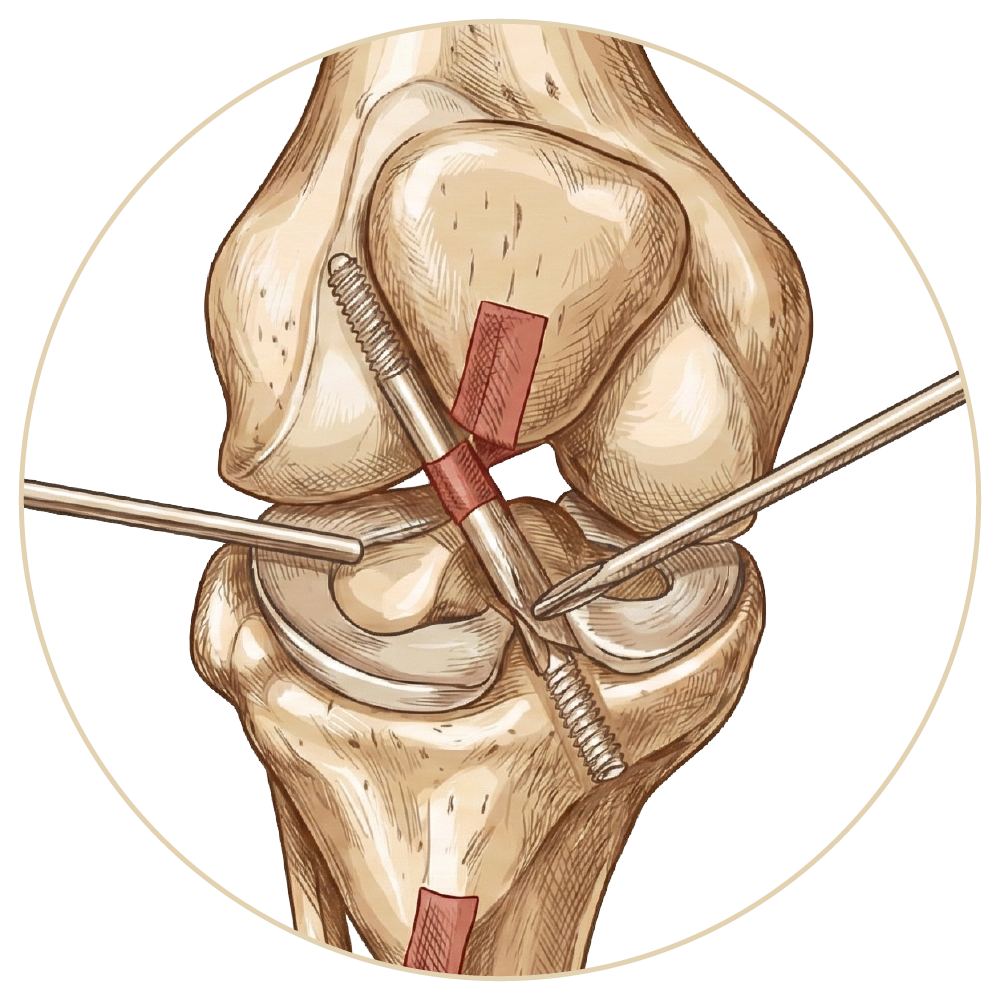

Arka Çapraz Bağ Ameliyatı

Ön Çapraz Bağ Ameliyatı

Menisküs Yırtığı

Menisküs Nakli

Kıkırdak Yaralanmaları

Diz Kireçlenme Tedavsi

Diz Artroskopisi